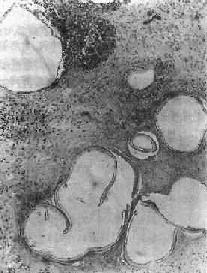

肝泡状棘球蚴病

图19-20 肝泡状棘球蚴病

可见多数大小不等的小囊泡,仅见角皮层而不见生发层,囊内无头节,囊泡间组织呈凝固性坏死